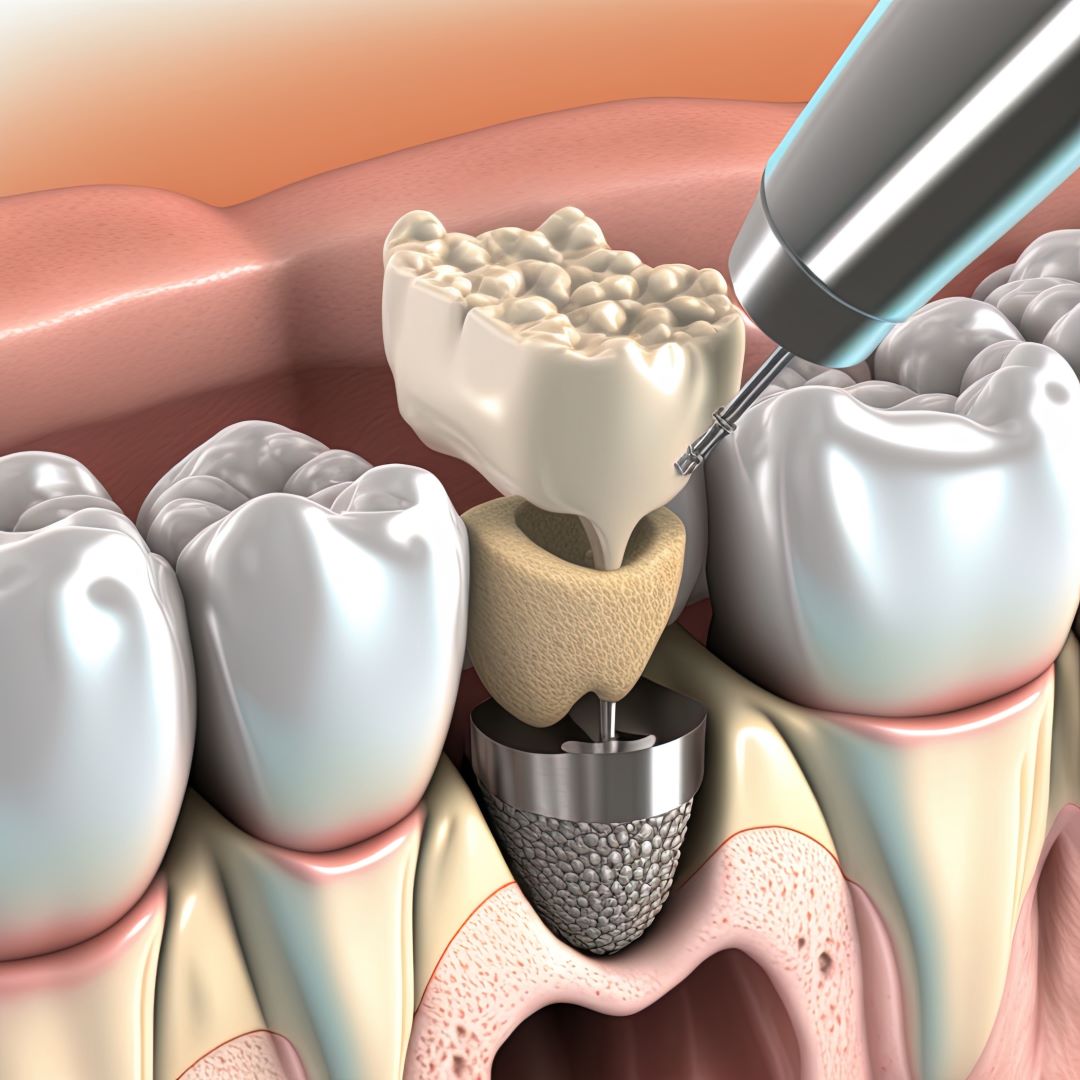

Reconstructions osseuses à visée implantaire

Lorsque l’os de la mâchoire est insuffisant pour soutenir un implant dentaire, des techniques de reconstruction osseuse peuvent être nécessaires. Ces procédures permettent d’augmenter le volume osseux pour garantir la stabilité de l’implant.

Voici les principales techniques :

- Greffe osseuse : Ajout d’os ou de matériaux pour augmenter le volume osseux.

- Régénération Osseuse Guidée : Stimule la repousse osseuse grâce à des biomatériaux.

- Sinus Lift : Augmentation de l’os dans la région des molaires supérieures par élévation des sinus.